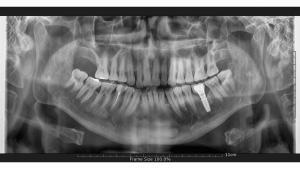

Upon arrival at our esteemed clinic in Marmaris, Turkey, patients seeking a full set of dental implants undergo a meticulous assessment, including a panoramic X-ray and oral examination. Our adept doctors analyze the examination findings meticulously to craft a bespoke treatment plan tailored to each patient’s unique needs. Subsequently, we embark on the implant surgery journey, committed to delivering unparalleled care and ensuring optimal treatment outcomes for our valued patients.